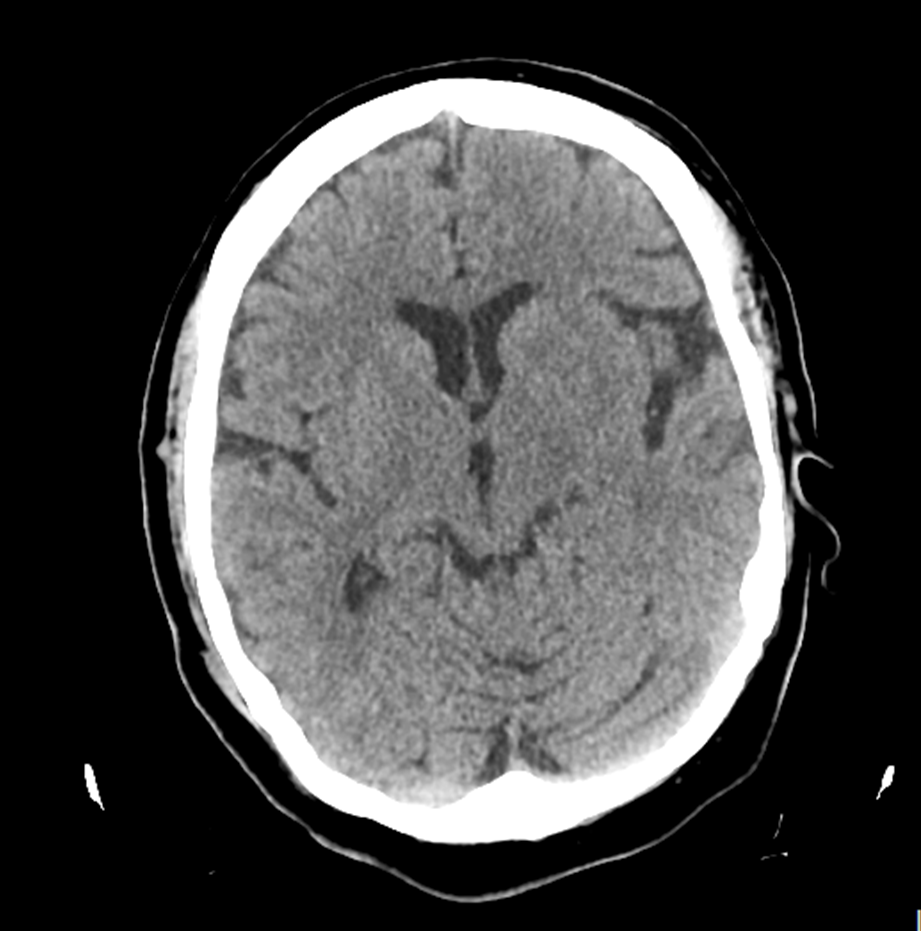

Paciente de 66 años de edad que ingresa por pérdida de fuerza súbita de extremidades izquierdas con hemiplejia derecha. En la urgencia se le realiza TAC cerebral: